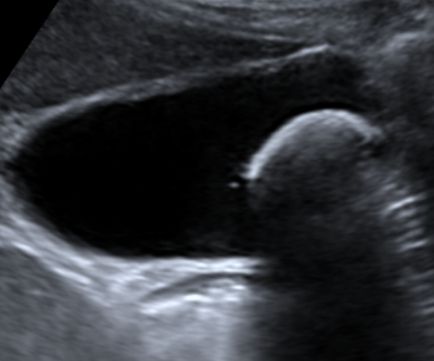

Safra kesesi varyasyonları, kesenin doğuştan gelen veya sonradan gelişen şekil bozuklukları olup; genellikle tesadüfen saptanırlar. Bu varyasyonlar arasında "Frigyalı şapkası" (kesenin bir kısmının kendi üzerine katlanması), kum saati görünümü veya çift safra kesesi gibi yapılar sayılabilir. Çoğu varyasyon klinik bir şikayete ya da yakınmaya yol açmasa da, nadiren safra akışını zorlaştırarak taş oluşumuna zemin hazırlayabilirler.